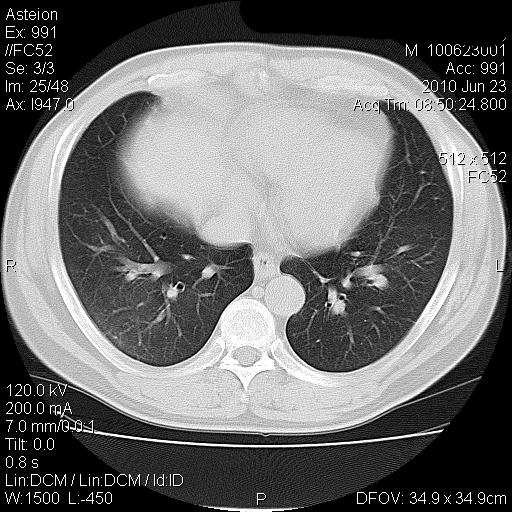

痰培养+药敏试验结果

耐甲氧西林金黄色葡萄球菌生长

敏感:头孢哌酮、舒巴坦、头孢曲松、头孢噻肟、阿齐酶素

耐药:万古霉素、笨唑西林、

中介:克林霉素

ppd试验阴性

患者消炎治疗(第三代头孢类)两周后复查ct片

两肺上叶及右肺下叶感染性病变;建议抗炎治疗后复查。结果消炎吸收